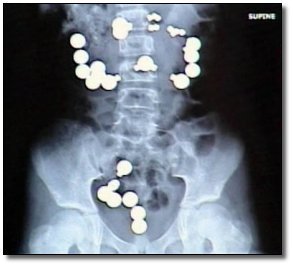

Os médicos do Hospital Geral do Estado levaram um baita susto quando esse Alagoano esfomeado entrou com uma queixa de fortes dores abominais e diarréia . Eles tiveram de operar um paciente, depois da endoscopia que mostrou um quadro um tanto confuso tamanha era a muvuca demonstrada. O que foi encontrado no estômago foi nada mais nada menos que cerca de 3 Kg de metais. Para piorar, um ímã juntava os metais e impedia que eles fossem liberados normalmente pelo organismo.

– Encontramos 22 chaves, um miolo de relógio, 4 pulseiras de relógio, oito moedas, 50 parafusos pequenos e quatro grandes, pregos, molas de pregador de roupa, quatro fusíveis, duas agulhas de costura, 31 pedaços de gilete e um pedaço de ímã, contou o médico, ainda surpreso, acrescentando que também foram achados uma tesoura, botões, linha e outros objetos metálicos.

– Nós recebemos aqui muitos casos de crianças que ingerem moedas. Fazemos radiografias e acompanhamos o caso até a eliminação delas. Mas, nesse caso, tinha um ímã prendendo os objetos, por isso decidimos fazer a cirurgia, explicou o cirurgião.